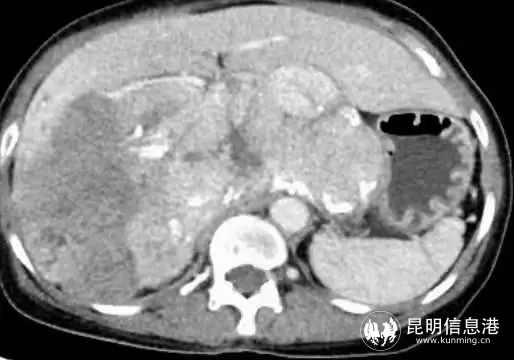

57岁的吴女士,从今年年初开始,感觉体力不断下降,白天易疲劳,提不起精神,胃口也不好,体型日渐消瘦,不久出现右上腹隐约疼痛症状。家人送医后CT检查结果显示:中、上腹巨大不均质肿物,填塞肝门,贴压胆囊、胰腺、右肾、门静脉、下腔静脉,考虑恶性。

图为术前影像

患者入院后,省三院肝胆胰外科专家团队经过仔细检查后发现该患者中上腹巨大不均质肿物已经填塞肝门,与肝实质分界不清,贴压胆囊、胰腺、右肾、门静脉、下腔静脉,手术操作的空间非常小。其次,患者身体基础条件十分不好,长期高血压,心肺功能极差,肝功能下降,手术难度极大。